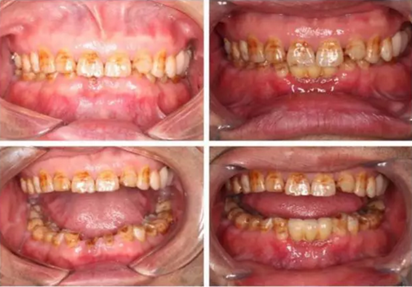

下圖是術后照片 治療過程 術前測量上下牙長度比例,確定水激光冠延長深度約3mm,拔除31、41,在術區(qū)減低牙槽嵴高度,32、42位點種植MINI型一段式種植體,使用臨時愈合帽行暫時性修復。

治療前后照片顯示患者上下臨床牙冠比例協(xié)調(diào),患者對臨時修復體效果十分滿意。當然有待后期愈合及長期的臨床隨訪,以觀察遠期臨床效果。將水激光應用臨床冠延長,有利于精準去除骨量,利于術后愈合。而MINI型一段式種植體滿足骨寬度不足,及臨時修復打下堅實基礎。